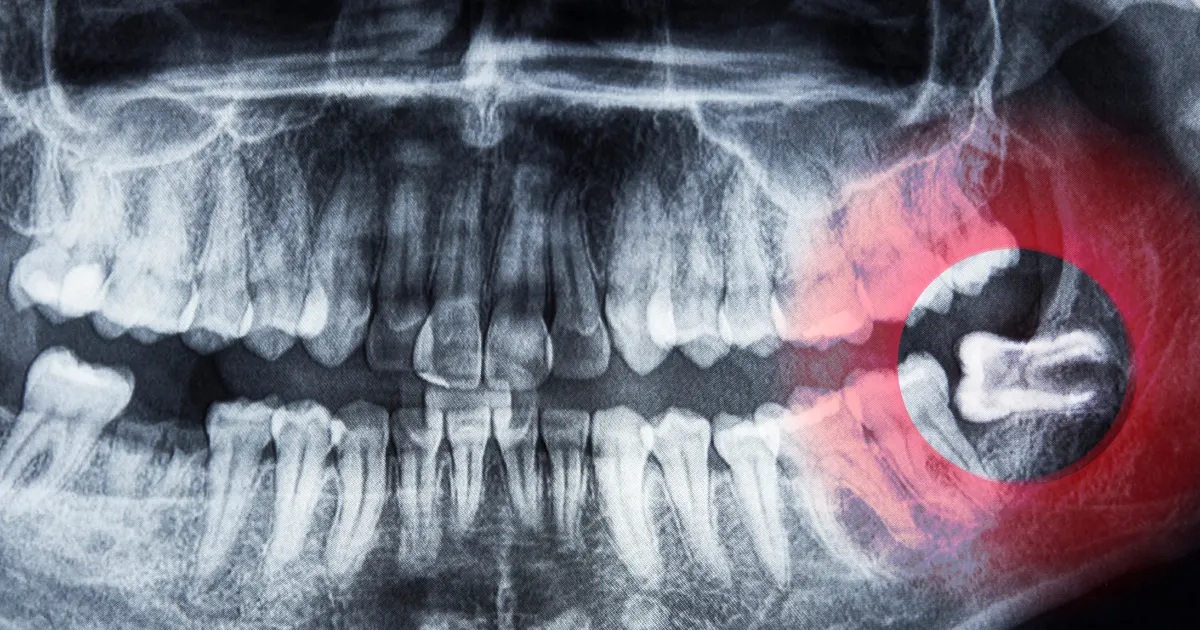

他の組織を傷つけるリスク

親知らずが神経や血管に近接して位置している場合、抜歯時にこれらの重要な組織を損傷するリスクがあります。

これは、感覚の喪失や出血などの重篤な合併症を引き起こす可能性があります。

そのため、抜歯前には詳細な画像診断が必要とされます。